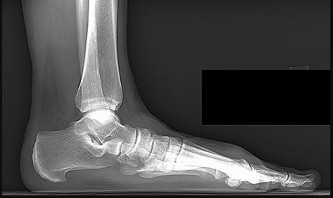

Prepare for the Arab Orthopaedic Board exam with high-yield MCQs, clinical cases, and comprehensive review materials.